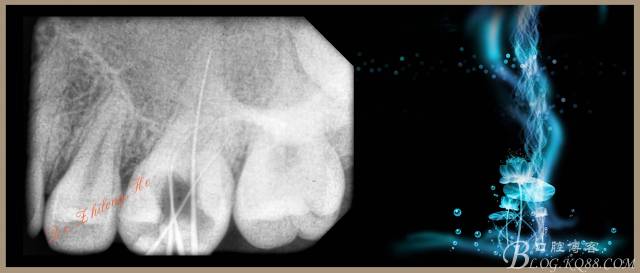

4、試主尖,側(cè)壓充填法根充,拍根充片,聚羧酸鋅暫封。

1、上頜磨牙近中頰根常有兩個根管,即MB、MB2,近年來研究表明上頜磨牙MB2的發(fā)現(xiàn)率大于60%,MB2的遺漏是上頜磨牙根管治療失敗的重要原因之一。熟悉、掌握MB2根管口的定位,有助于臨床醫(yī)師發(fā)現(xiàn)MB2,提高上頜磨牙根管治療的成功率。下面是MB2根管口的定位方法(僅供參考):

①MB-MB2距離為(1.47±0.54)mm;

②MB-P的距離為(5.77±0.66)mm;

③MB2根管口與MB-P連線的垂直距離為(0.53±0.28)mm;

④MB-P連線與MB-MB2連線的夾角為23.07°±13.08°;

⑤MB2位于MB舌側(cè)2mm以內(nèi)及MB-P連線近中1mm以內(nèi)。